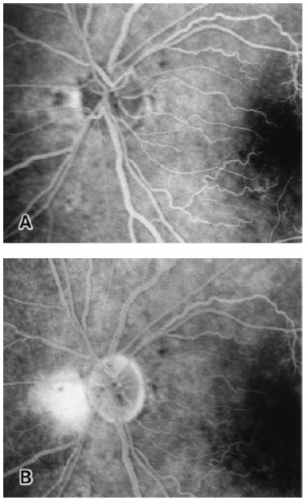

Other theories included hemorrhagic CSF directly being transmitted through the optic nerve sheath [22] or around perivascular spaces [23]. However, this are not supported anatomically by the absence of a known channel between these spaces [24] and by patients with confirmed Terson syndrome without intracerebral hemorrhage. In addition, fluorescein angiography demonstrates leakage at the disc margin in patients with Terson syndrome with vitreous hemorrhage [25]. This suggests rupture of blood vessels as opposed to transfer of hemorrhage through the optic nerve.

Loss of red reflex is seen in 20% of eyes with Terson syndrome[2]. B-scan may be used to confirm vitreous hemorrhage when no view to the fundus is present (Fig. 4). Orbital CT scan may detect Terson syndrome in two-thirds of cases, showing retinal crescentic hyperdensities and retinal nodularity [43][28].